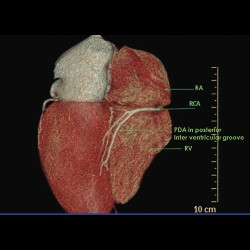

Normal Proximal Coronary Artery Diameters in Adults

Normal Proximal Coronary Artery Diameters in Adults from India as Assessed by Computed Tomography Angiography

READ MORE

Normal Proximal Coronary Artery Diameters in Adults

Normal Proximal Coronary Artery Diameters in Adults from India as Assessed by Computed Tomography Angiography

READ MORE